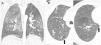

La TC torácica en espiración es una técnica complementaria de la inspiración que aporta valiosa información fisiológica y puede ser más sensible que las pruebas de función respiratoria para detectar atrapamiento aéreo. Tiene múltiples indicaciones, entre las más frecuentes están la enfermedad obstructiva de la vía aérea producida por bronquiolitis obliterante, asma, síndrome de Swyer-James, traqueomalacia, neumonitis por hipersensibilidad o sarcoidosis. En alguna de ellas, como la bronquiolitis obliterante, la TC espiratoria puede ser la única técnica de imagen que detecta alteraciones en las fases iniciales. Si queremos que sea de utilidad diagnóstica, hay que asegurarse de que el estudio tenga calidad suficiente. Para ello se recomienda explicar al paciente en qué consiste la prueba, emplear instrucciones precisas y realizar un breve entrenamiento antes de iniciar la adquisición. En este trabajo sugerimos estrategias para optimizar la técnica y proponemos un algoritmo para interpretar los hallazgos radiológicos en el contexto de la patología obstructiva pulmonar.

Expiratory CT scan is a complementary technique of inspiratory CT that provide valuable physiological information and may be more sensitive to detect air trapping than pulmonary function tests. It is useful in many obstructive airway diseases, including obliterative bronchiolitis, asthma, Swyer-James syndrome, tracheomalacia, hypersensitivity pneumonitis and sarcoidosis. In obliterative bronchiolitis, expiratory CT scan may be the only imaging technique that shows abnormalities in the early phase of disease. In order to obtain a good quality study, we should explain the procedure to the patient, use precise instructions and do some practice before image acquisition. Here we describe strategies to optimize the technique and propose an algorithm that help in interpretation of imaging findings in patients with obstructive airway disease.